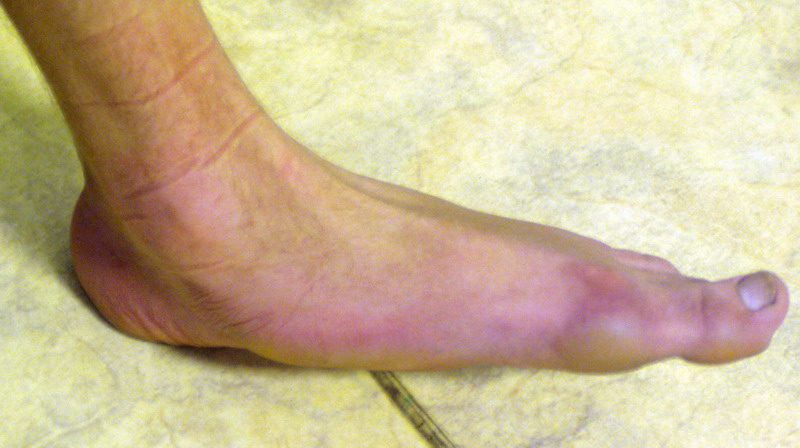

Пациент 15 л., болезнь Литтля, спастический нижний парапарез, интеллект высокий. Ребенок настроен на активный образ жизни. С недавнего времени начал ходить без дополнительной опоры. Появилась проблема с левой стопой - во время ходьбы опора приходится на смещенную кнутри таранную кость.

Может образоваться болезненный натоптыш или язва. Общепринятой операцией является трехсуставной артроде с мобилизацией таранной кости. Выполнять такую операцию у спастика и в раннем возрасте проблематично. Родстьвенники тем более готовы материально и морально осуществить хирургическое лечение за рубежом, если оно показано и возможно. Предпочтительно в Австрии и Германии. Если кто-то посоветует координаты таких клиник - были бы признательны.